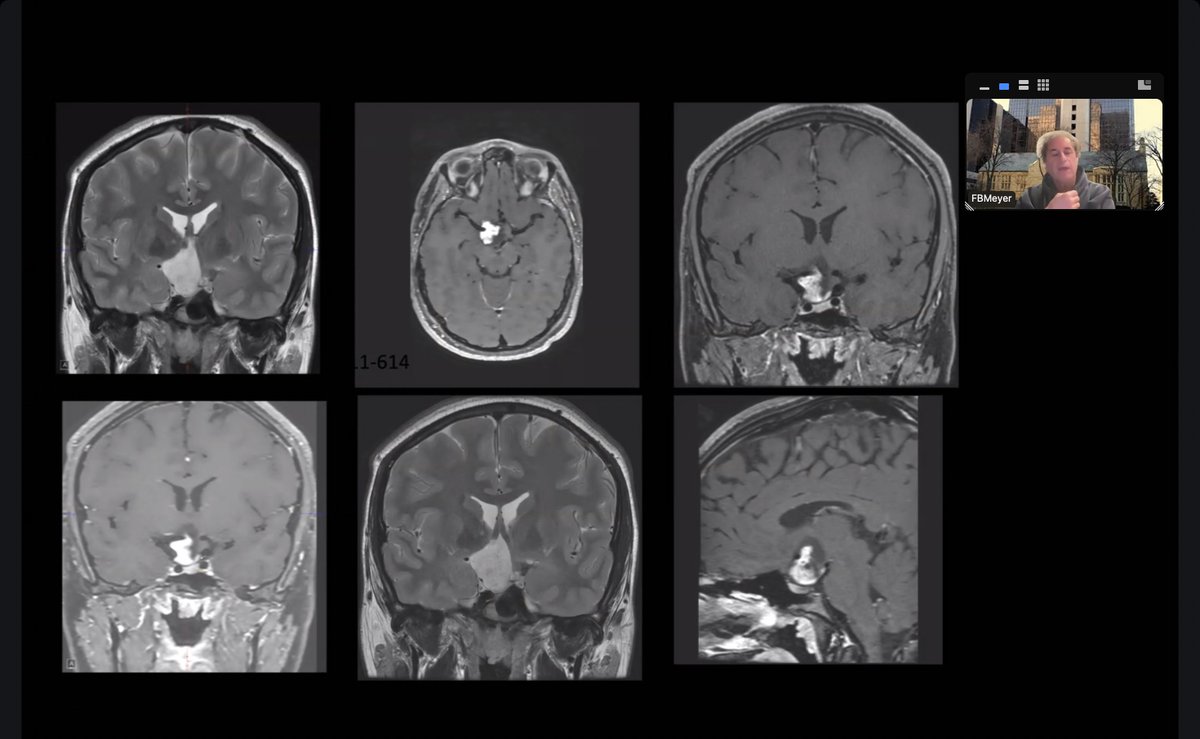

What better way to close out Journal Club this semester than with an incredible presentation by Damirez Fossett! We explored standard neurosurgical approaches and wrapped up with insightful discussion & bright smiles. Shoutout to Dr. Fossett & Dr. Meyer for a great year!👏

What better way to close out Journal Club this semester than with an incredible presentation by <a href="/DamirezFossett/">Damirez Fossett</a>! We explored standard neurosurgical approaches and wrapped up with insightful discussion &amp; bright smiles. Shoutout to Dr. Fossett &amp; Dr. Meyer for a great year!👏